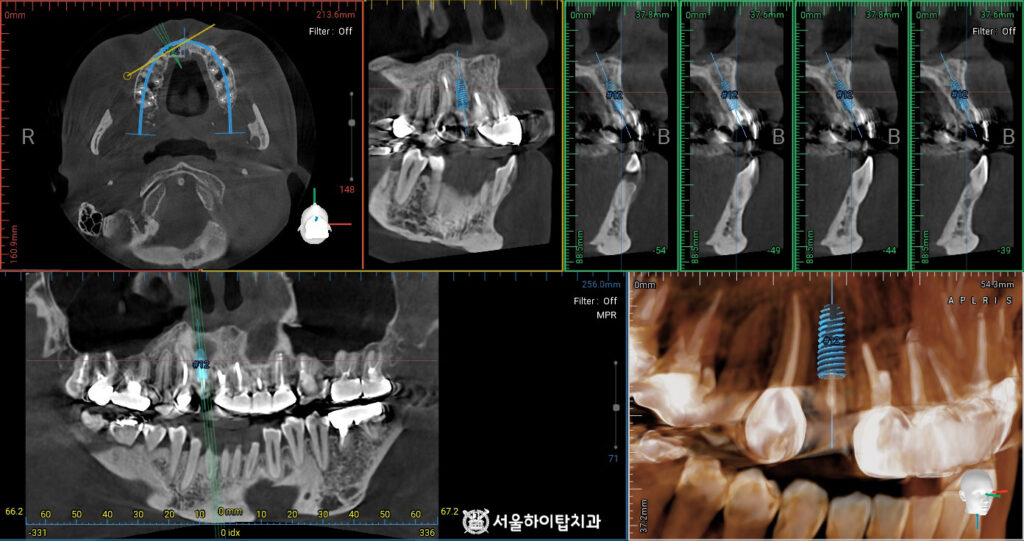

CT 기반 임플란트 가상 식립 시뮬레이션

먼저 임플란트 수술에 들어가기 전, 픽스처를 가상으로 식립해 볼 수 있습니다.

백운역 치과 에서는 이를 통해

치조골의 두께와 형태, 신경관 위치, 인접 치아와의 간격 등을 미리 확인할 수 있어,

수술 중 발생할 수 있는 위험을 최소화할 수 있다고 설명해 드립니다.

또한 최적의 위치와 각도를 계획함으로써,

수술 후 임플란트의 안정성과 장기적인 예후를 높일 수 있습니다.

현재 남아 있는 골량은 충분하지만, 치근만 발치해야 하는 상황이므로

버(Bur)를 사용하여 치근을 분할한 후 발치하고, 이어서 임플란트를 식립하게 됩니다.